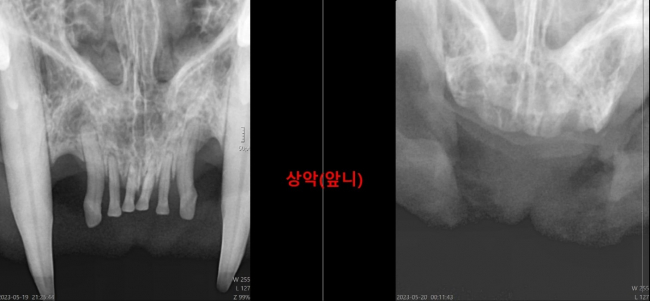

| 치료과정 | 5/15(월) 포획을 하여 5/16(화) 오전 병원에 내원했는데 육안으로 보기에 안쪽 잇몸은 당연하고, 앞니 쪽 잇몸까지 모두 염증이 매우 심했습니다. 그래서 이 경우 전발치가 필요하다는 소견이셨습니다. 수술이 꽤 오래 걸리다보니 당장 수술은 어렵고, 잇몸 상태가 좋지 않아서 5일정도 약을 먹으면서 조금이라도 염증을 가라앉힌 후에 수술하는 것을 권하셨고, 상태가 심각한 만큼 수술 일정을 빨리 잡아주셨습니다. 수술은 5/19(금) 밤늦게 시작되어 12시를 넘겨 새벽에 끝이 났습니다. 전발치는 엑스레이로 확인했을 때 잔존 뿌리 없이 깨끗하게 모두 되었음을 확인하였고, 목 안쪽까지 염증이 매우 심해서 목 안쪽은 건드릴 수 없으셨다고 합니다. 진통제 주사를 맞고, 항생제와 스테로이드, 진통 물약 등을 처방받아 퇴원하였습니다. 5/25(목) 현재는 건사료, 습식캔, 물 모두 잘 먹습니다. 이따금씩 밥을 먹을 때 입을 벌리는걸 봐서는 아직 통증이 남아있기는 한 것 같지만, 밥도 잘 먹고 잘 자고 여기저기 오르락 내리락 하면서 잘 지내는 걸 보면 활력도 좋습니다. |